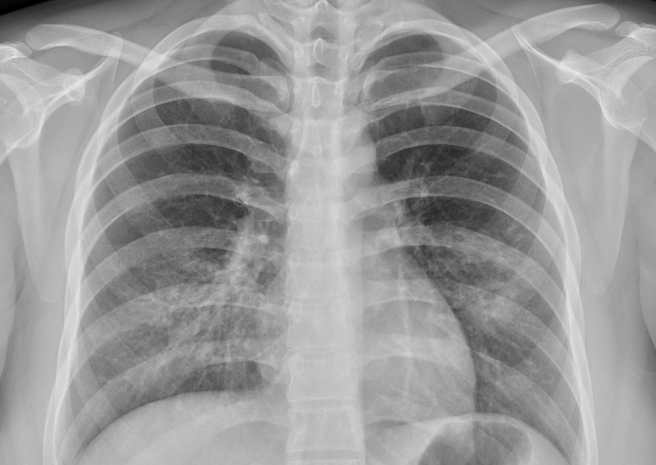

苏一峰指出,这位台湾女病患的症状较严重,年纪轻轻就出现咳血的情形,X光也明显呈现「毛玻璃肺炎」,感觉已经感染肺炎一阵子了。